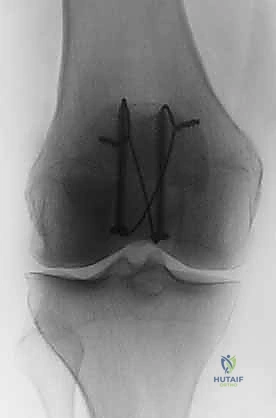

كسر الرضفة: دليل شامل لعملية التثبيت الداخلي بالأسلاك (ORIF) مع الأستاذ الدكتور محمد هطيف

الأشعة السينية (X-rays): هي الخطوة الأولى والأساسية. يتم أخذ صور من زوايا متعددة:

- المنظر الأمامي الخلفي (AP View): لتقييم النمط العام للكسر.

- المنظر الجانبي (Lateral View): حاسم جداً لتقييم مدى تباعد أجزاء الكسر (Displacement) وعدم انتظام السطح المفصلي (Articular step-off).

- منظر السماء (Skyline View): مفيد لرؤية الكسور الطولية وتقييم التمفصل بين الرضفة وعظم الفخذ، ويتم إجراؤه إذا كانت حالة المريض تسمح بثني الركبة قليلاً.

الدليل الشامل لعملية التثبيت الداخلي بالأسلاك (ORIF with Tension Band Wiring) خطوة بخطوة

تُعتبر تقنية "شريط التوتر" (Tension Band Wiring - TBW) المعيار الذهبي والأكثر استخدامًا في علاج كسور الرضفة المستعرضة. تعتمد هذه التقنية الميكانيكية العبقرية على تحويل قوى الشد (Tensile forces) التي تولدها العضلة الرباعية في الجزء الأمامي من الرضفة، إلى قوى ضغط (Compressive forces) تفيد في التئام الكسر في الجزء الخلفي (المفصلي).